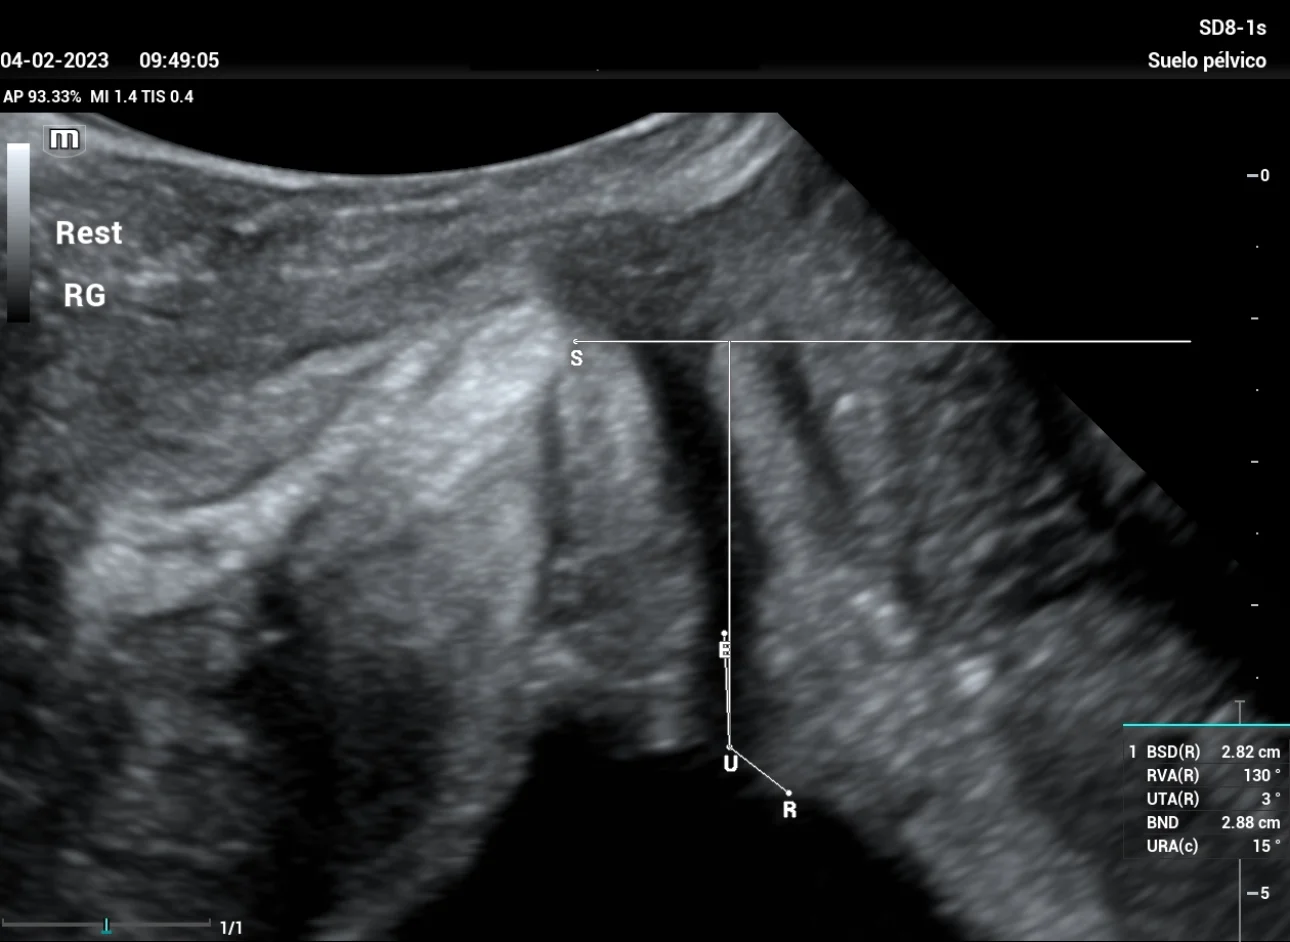

A study was carried out with filling bladder of 300 ml. The reference line is set at the inferior margin of the symphysis pubis, giving a total result of Bladder neck descent (BND) of 28mm, a UTA angle of 3º and a beta angle (RVA) of 130º (Figure 1), both within normal parameters, we performed the Valsalva maneuver showing a 26mm descent, and after maneuvering of Valsalva (Figure 2) a UTA angle of 13º (10º rotation) is observed, RVA of 98º.

stress-urine-fig1

Figure 1: The image corresponds to the mid- sagittal section of the pelvic floor at rest, with magnification that allows for the correct identification of the different structures to be studied (symphysis pubis, bladder floor, and urethra), with the measurement of the UTA and RVA angles.